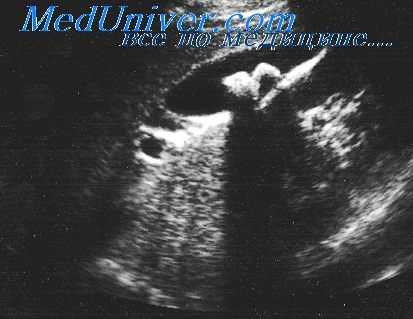

На снимке а показаны четыре камеры сердца: ПП, ПЖ, ЛП и левый желудочек (ЛЖ). На представленном снимке, сделанном во время диастолы, видны также межжелудочковая перегородка и передняя створка митрального клапана. Здесь имеет место II степень обнаружения газовых пузырьков, причем последние видны как белые пятнышки в просвете ПЖ. Венозные газовые пузырьки обозначены как ВП. Заметьте, что ЛП и ЛЖ свободны от газовых пузырьков. В конце диастолы (снимок б) артериальный газовый пузырек (АП) появляется в ЛЖ.

Во время систолы (снимок в) видно, как этот газовый пузырек начинает быстро двигаться в сторону аортального протока. На приведенном снимке артериальный газовый пузырек виден как группа ярких пятнышек. Это происходит вследствие некоторого разложения яркости во времени, характерного для процесса оптического преобразования, применяемого при переводе ультразвукового изображения в обычное телевизионное. Расстояние между пятнышками соответствует перемещению пузырька за 1/60 с Обратите также внимание на движение ВП во время различных фаз сердечного цикла.